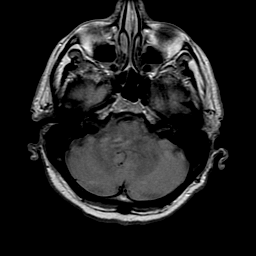

1. MRI(磁共振成像)

原理:

- 利用强磁场(0.5-7特斯拉)和射频脉冲激发人体内的氢原子核(¹H)

- 通过接收原子核弛豫过程中释放的射频信号重建图像

- 主要参数:T1加权(解剖结构)、T2加权(病理改变)、FLAIR(抑制脑脊液信号)

优势:

- 无电离辐射

- 软组织分辨率极高(可区分灰质/白质)

- 多参数成像(DWI显示扩散受限,MRA血管成像)

- 任意平面成像(矢状/冠状/横断)

局限:

- 检查时间长(30-60分钟)

- 对金属植入物敏感(起搏器禁忌)

- 骨皮质显示较差

临床应用:

- 神经系统疾病(脑肿瘤、脱髓鞘病变)

- 关节软骨/韧带损伤

- 腹部器官(肝脏脂肪定量)